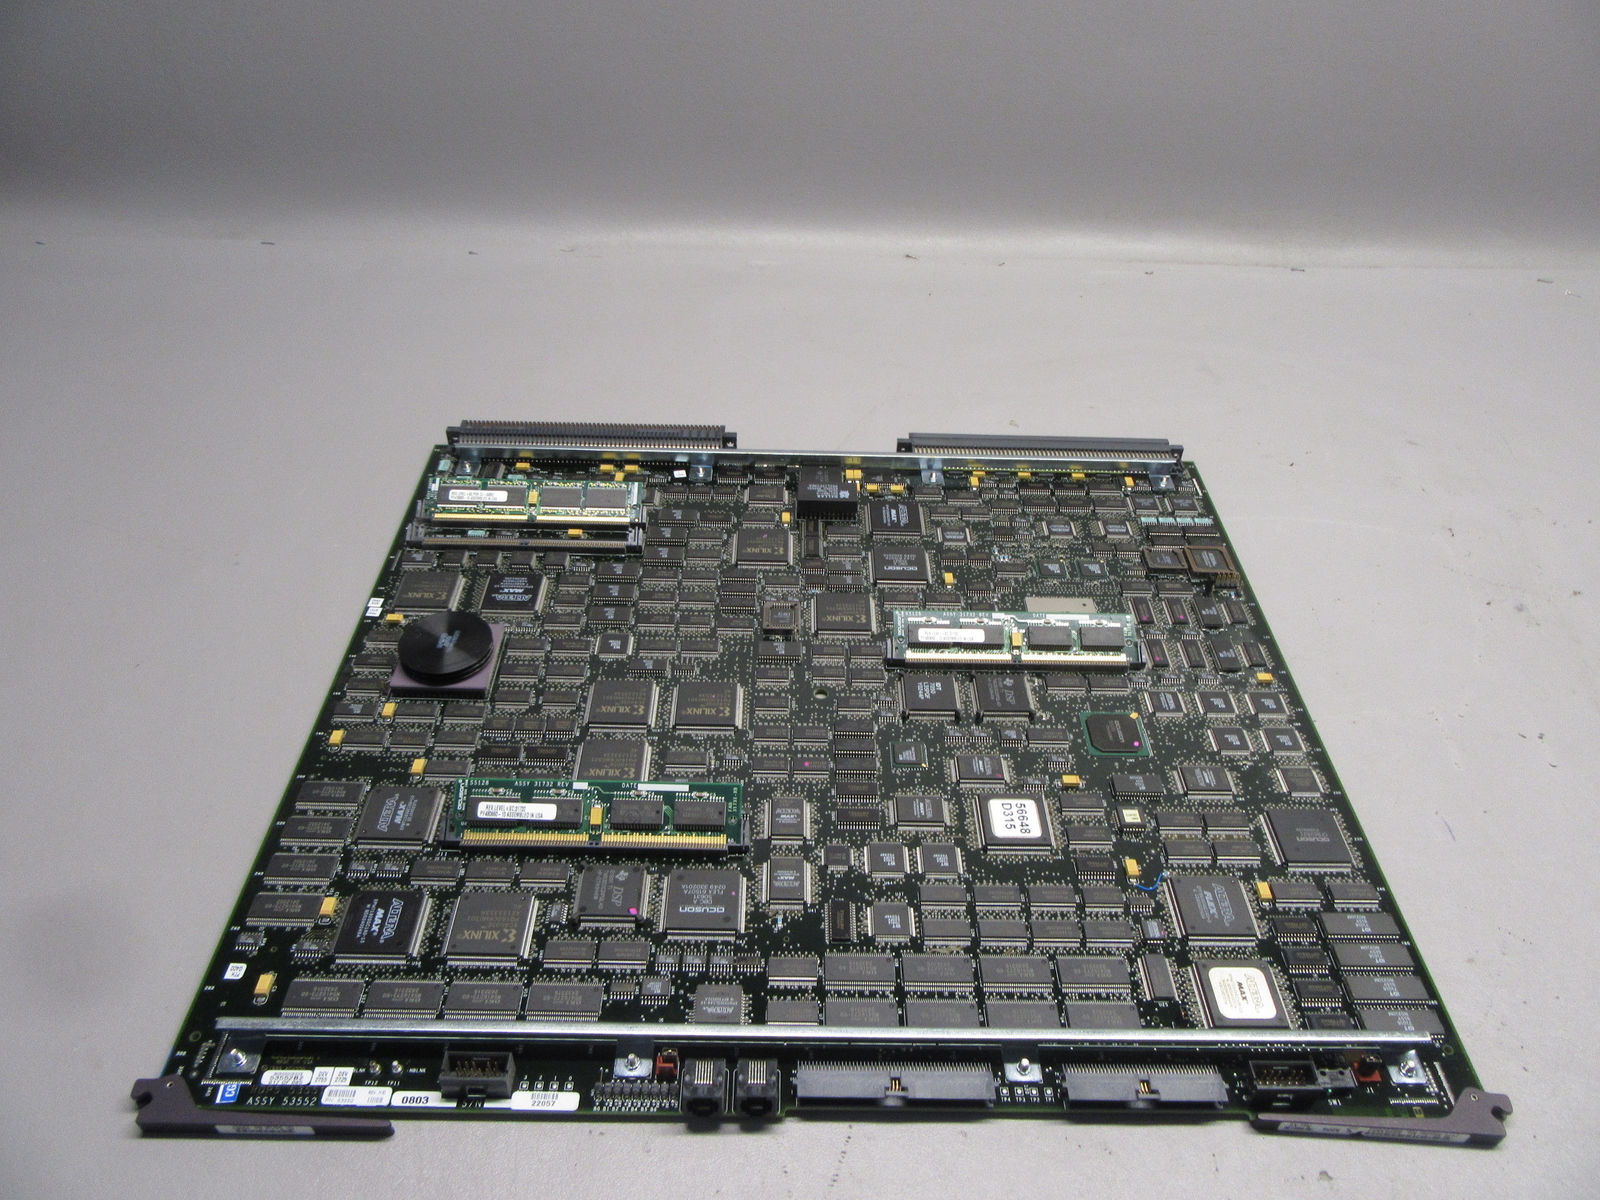

Acuson Probes

DIAGNOSTIC ULTRASOUND MACHINES FOR SALE